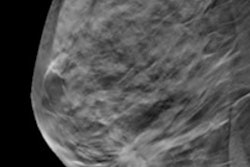

The prototype also struggled with ABUS image quality. The reading radiologist rated most ABUS scans as having well-distinguishable tissue structures but a lower quality than handheld ultrasound. A total of 7% of lesions were also only partly visualized on ABUS and 11% were classified as BI-RADS 0 due to low image quality.

The team chalked up the image quality issues to the transducer, noting they will need to adapt a high-end transducer in order to improve images acquired with the prototype. Fortunately, they're already working on that for version 3 of Fusion-X-US.